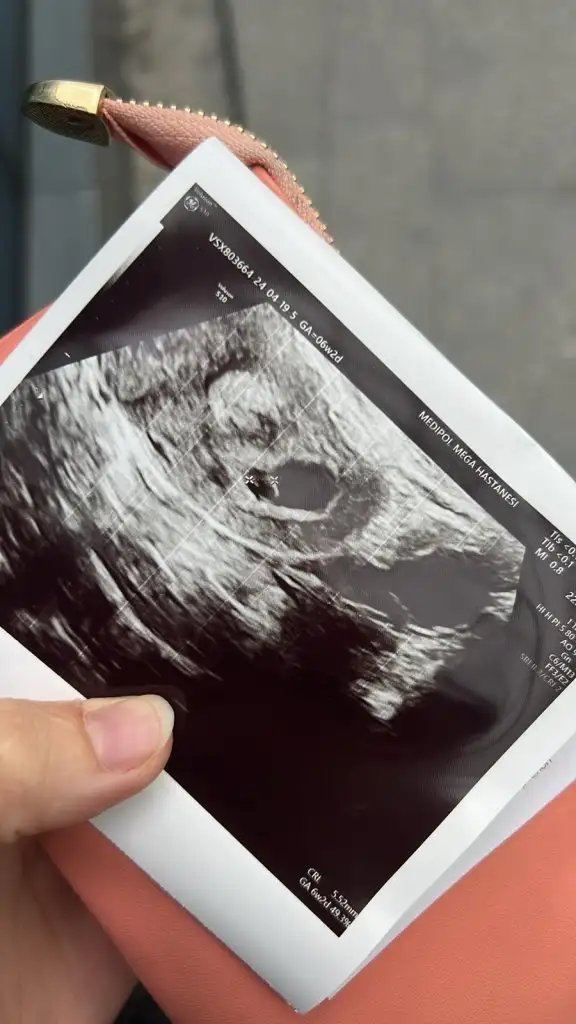

Merhabalar benimkini de yorumlayabilir misiniz acaba 🤗🤗 10+1 haftalık burda. Ama 6-7 gün fazla büyümüş yani 11+1 gibi 🤗🥰